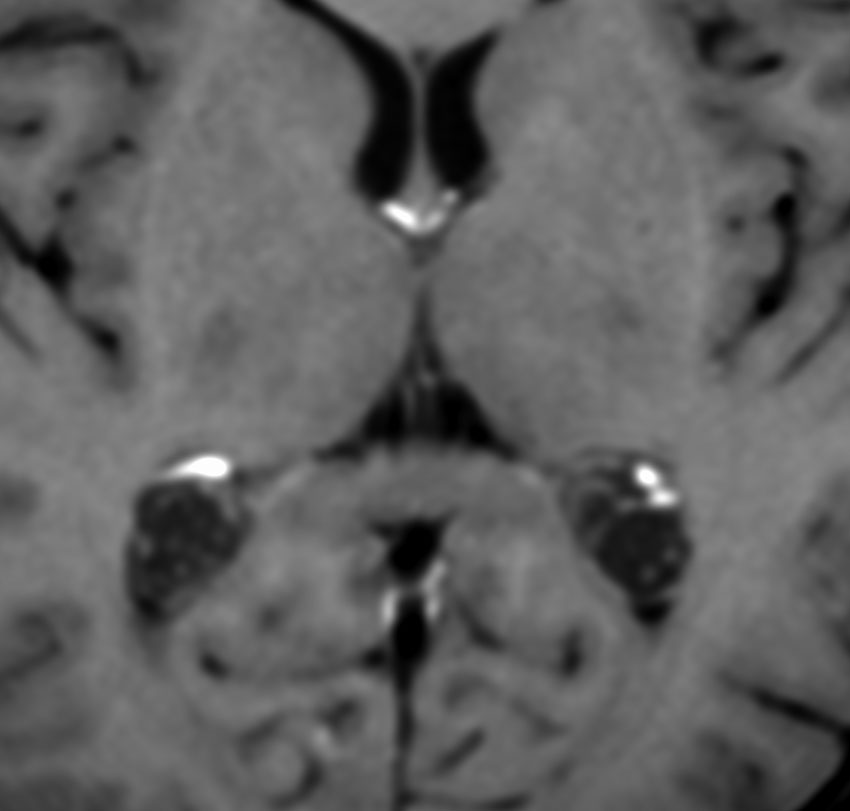

脳ドックなどでたくさん発見されるものです。両側に見られることが多いです。この患者さんは右側脳室の脈絡叢乳頭腫と診断されて来院されました。でも両側脳室三角部の脈絡叢のう胞です。右はガドリニウム増強ですが造影されません。これは経過観察の必要もなく放置してよいものです。